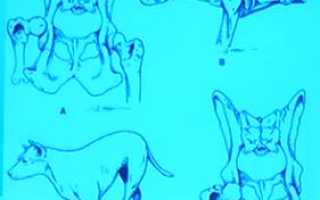

Ветеринары часто сталкиваются не только с вывихом, но и с другими травмами конечностей, например, разрывом связок. Врожденные патологии тазобедренного сустава могут указывать на дисплазию (смещение бедра). Больной щенок не может полноценно двигаться и запрыгивать на предметы, часто лежит с разведенными в стороны бедрами, как лягушка. С возрастом симптомы дисплазии усиливаются: появляется боль в тазобедренном суставе, особенно при ощупывании, и хромота. Собака все реже двигается, а при движении задняя часть тела как бы вихляет.

Вывихи бывают врожденными и приобретенными (травматическими), полными и частичными (подвывихами).

У собак чаще всего встречается полный травматический вывих головки тазобедренного сустава в краниодорсальном положении (94% случаев) и каудовентрально по направлению к запирательному отверстию. Неполный вывих (подвывих) наблюдается у собак с дисплазией сустава.

Суть методики заключается в фиксации тазобедренного сустава в правильном анатомическом положении с помощью металлической спицы, которая проходит через сустав и фиксирует его к дну вертлужной впадины (фото 2). В послеоперационный период животное ограничивают в движении: разрешены кратковременные прогулки на коротком поводке и содержание в ограниченном пространстве. Через 2-3 недели спицу удаляют, а сустав стабилизируется благодаря образованию околосуставной фиброзной ткани. Функция конечности постепенно восстанавливается.

Операция заключается в удалении головки бедренной кости, после чего сустав стабилизируется за счет образования фиброзной ткани в его полости (фото 3). Владельцам может быть трудно понять, как возможно восстановление функций конечности после удаления сустава. Чтобы это прояснить, обратим внимание на прикрепление грудной конечности к скелету: между лопаткой и осевой частью скелета нет сустава, и соединение осуществляется только через мягкие ткани (синсаркоз). То же самое происходит и с тазовой конечностью после операции.

Операция показана пациентам с вывихами на фоне дисплазии тазобедренных суставов и массой тела до 15 кг. Преимуществом данной процедуры является отсутствие имплантатов внутри сустава. Сроки восстановления зависят от массы тела животного: чем она меньше, тем быстрее восстанавливаются функции конечности.